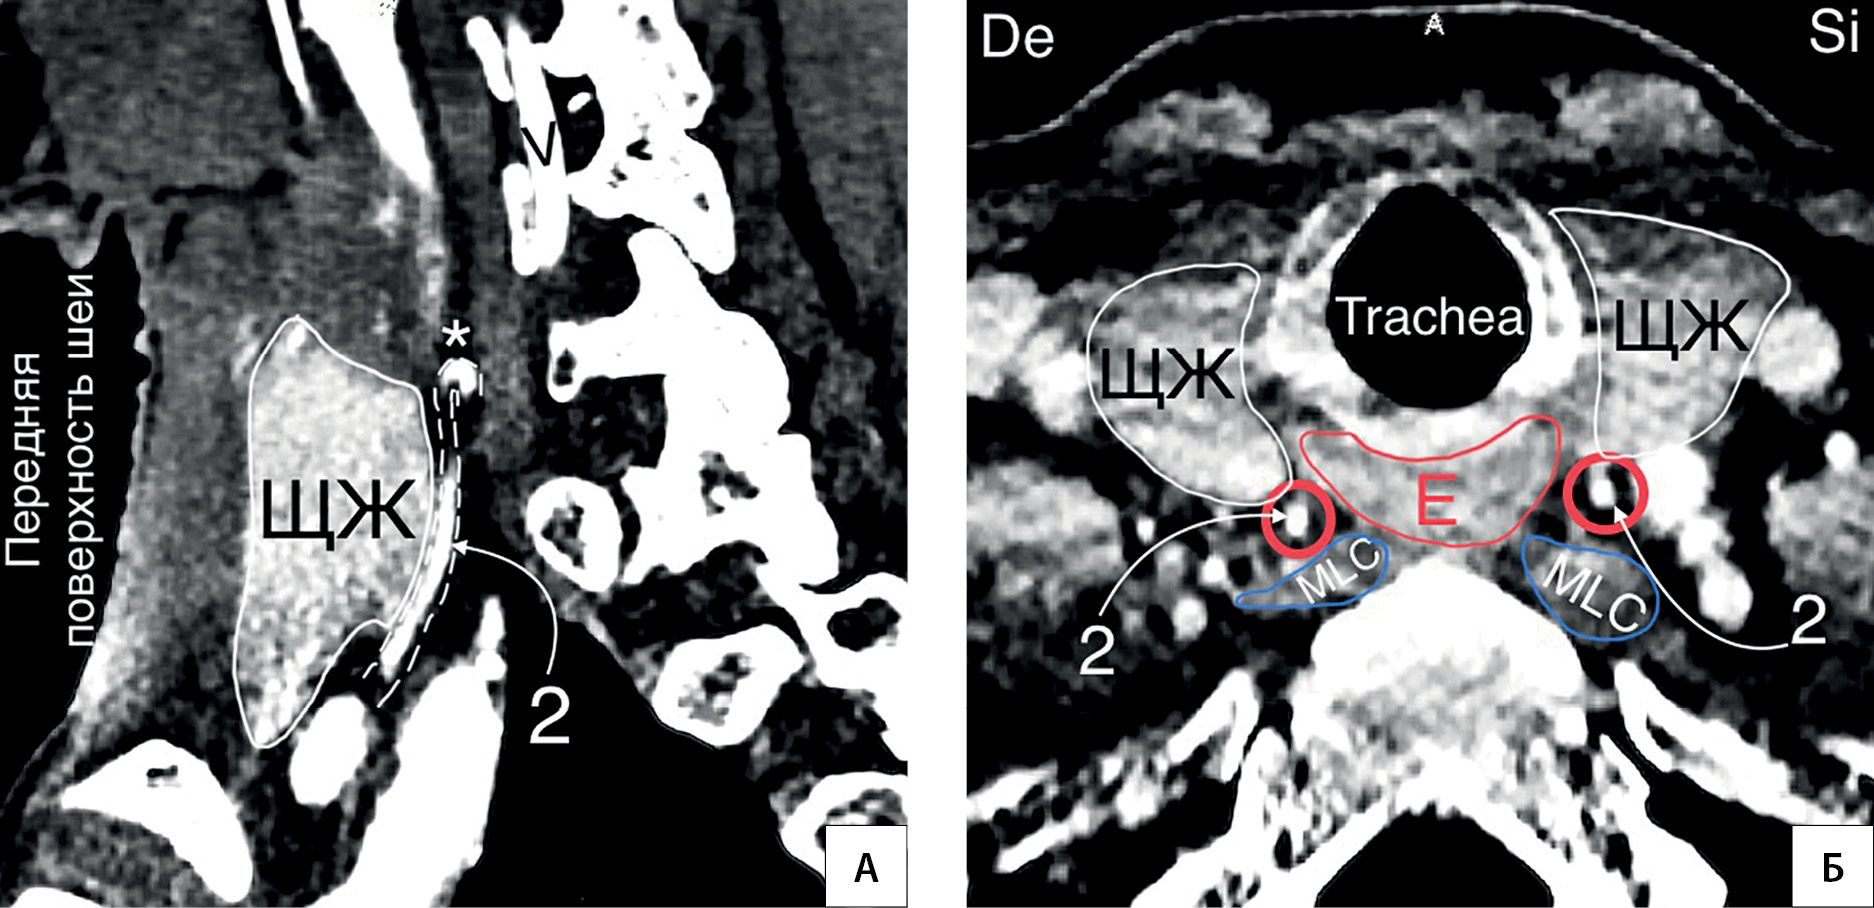

5. Рисунок 5. Колено НЩА располагается на уровне верхней трети доли ЩЖ. А — КТ-ангиограмма (сагиттальный срез); Б — КТ-ангиограмма (горизонтальная плоскость). * — колено НЩА; C — a. carotis communis; V — a. vertebralis; MSA — musculus scalenus anterior; MLC — musculus longus colli; De — dextra; Si — sinistra. | |